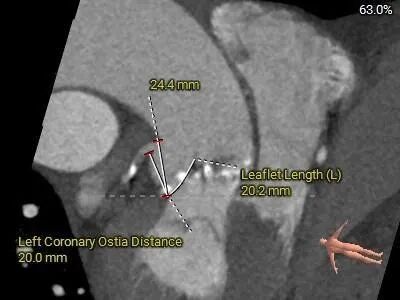

术前CT评估

Type0型二叶式主动脉瓣,LVOT偏敞口型,非横位心。

重度钙化,HU 850积分1711mm3。

左冠18.8,右冠19,综合分析冠脉阻挡风险适中。

瓣上多平面分析。

•Type0型二叶瓣,左右冠脉异窦,瓣叶增厚伴重度钙化,钙化团块主要沿双侧瓣叶分布,无窦下部分钙化延伸至LVOT,预估假体瓣膜植入锚定难度适中,受钙化块挤压,存在瓣膜移位及瓣周漏可能,同时需防范根部撕裂风险,

•左、右冠高度可,切线位测量,无冗长瓣叶,结合瓦氏窦、STJ内径综合预估,冠脉阻塞风险适中,